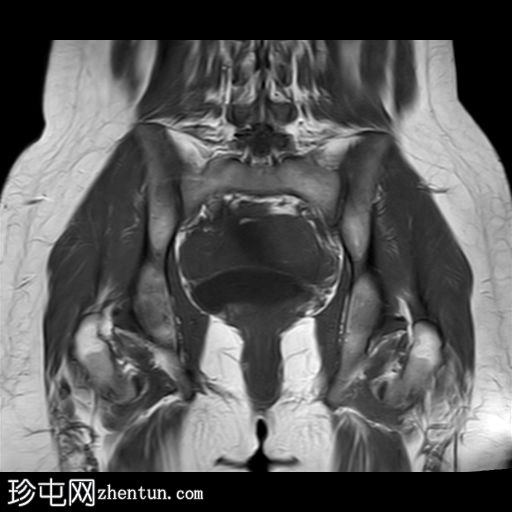

冠状位

T2加权像

右侧卵巢增大,卵泡呈周边排列。

附件血管蒂扭转(漩涡征)。

右侧附件旁可见一较大的、边界清晰的盆腔囊性病变,向右倾斜,提示为卵巢旁囊肿。

本病例展示了卵巢扭转的典型影像学特征,包括卵巢增大、卵泡呈周边移位、卵巢向内侧偏移以及特征性的漩涡征。

在这种情况下,较大的卵巢旁囊肿被认为是发生卵巢扭转的高危因素。如果卵巢旁囊肿较大(>5厘米)或活动度较大,其重量/活动度增加会牵拉附件,导致卵巢和输卵管发生扭转。